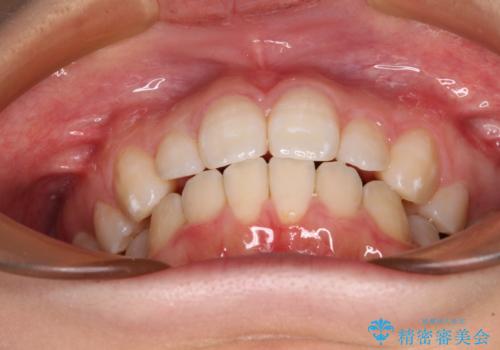

- 30代女性

- 下顎前歯を中心に、以前行った矯正治療の後戻りが気になるとのことで来院された患者様です。

後戻りは軽度であったため、インビザライン・ライトにて治療を行うこととしました。